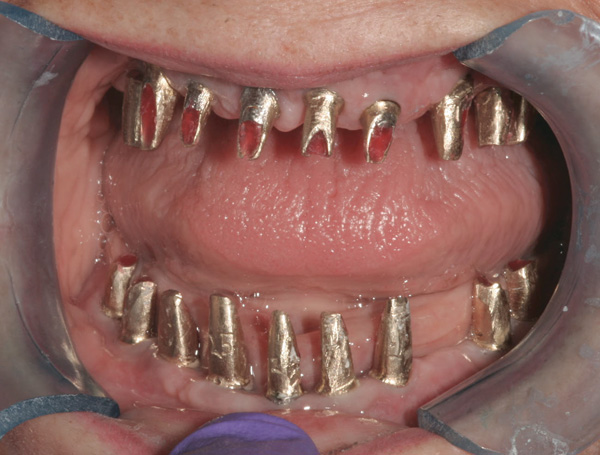

Background: This patient had a failing maxillary dentition and refused to wear a removable prosthesis. A staged approach was employed to retain some of his natural tooth abutments, and recession was noticed at the time of the impression for the second group of implants. Figure 1 shows the patient following insertion of the first set of implant custom abutments; the adjacent natural teeth are still present to support the provisional bridge. Seven months later, as shown in Figure 2, those first-stage custom abutments exhibited evidence of 1 mm to 3 mm of recession.

Figure 1  Patient following insertion of first set of implant custom abutments.

Figure 1

Figure 2 After 7 months, the first-stage custom abutments exhibited evidence of 1 mm to 3 mm of recession.

Figure 2